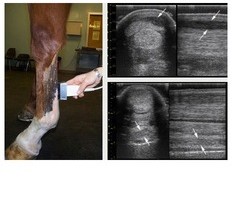

BEMVS has an ultrasound machine with 3 probes, this allows for imaging of tendons, the chest, abdomen etc as well as examinations per rectum (follicle scans, pregnancy diagnosis etc). The ultrasound machine is always in the car and available for use at a moments notice. Mare follicle scans and pregnancy diagnosis require the use of … Continue reading Ultrasound